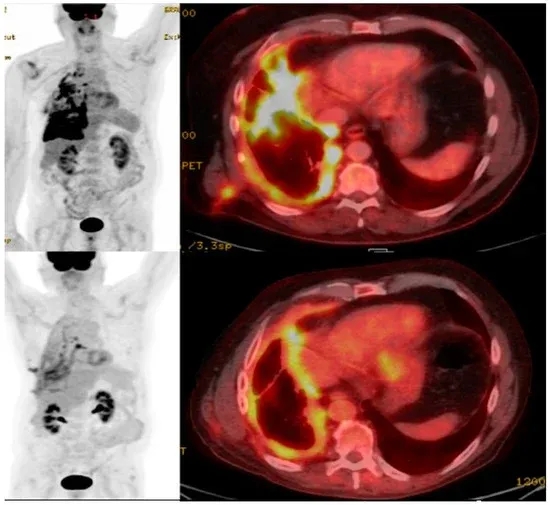

除此之外,既往还报道过一则CAR-T疗法治疗肺癌的振奋案例:一名68岁男性非小细胞肺癌患者,治疗前右侧胸膜存在高摄取转移灶;在接受包含CAR-T细胞疗法的全身治疗后,PET/CT检查显示转移灶高摄取信号明显缩小,直接印证治疗有效。

▲图源“MDPI”,版权归原作者所有,如无意中侵犯了知识产权,请联系我们删除